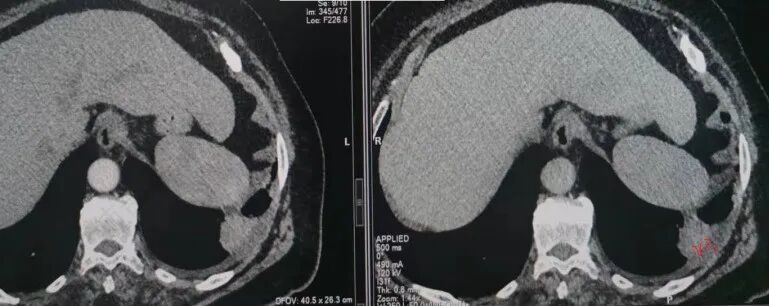

南边:今天的病例肺内部分基本都是炎性特点,问题就在于胸膜。

糊墙:肺内病灶不侵犯壁层胸膜或以外,与壁层胸膜相对而言分界清楚。

栽赃:病灶侵入壁层胸膜及胸膜外脂肪间隙、胸壁其他结构等,相对在病灶中央区域,与胸膜分界不清。

南边:看肺内病灶与胸膜分界清,增强后强化不一致,需要综合分析。

这是糊墙。

这就栽赃。都突到外面去了。

今天的病例有些伪影。

看起来就觉得放射状伪影。

我就不知道这些是胸水,伪影导致密度增高?还是胸膜增厚?

我只是邓较瘦:今天平扫的像栽赃, 增强感觉是增厚的胸膜。

南边:一般这类侵袭,是中央地带毛刷状延伸到胸膜内。

而且旁边这么宽的少,所以觉得很奇怪,不太符合,我是怀疑与照片有关。

你对比一下两侧的密度。肌肉密度不一样。